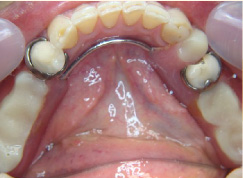

入れ歯は残っている歯に針金を引っ掛けるのが欠点。歯に負担をかけ見た目にも入れ歯と分かってしまう。針金を使わない入れ歯なら見た目だけではなく、歯にも負担が少ないですよ。

- 施術前

- 施術後